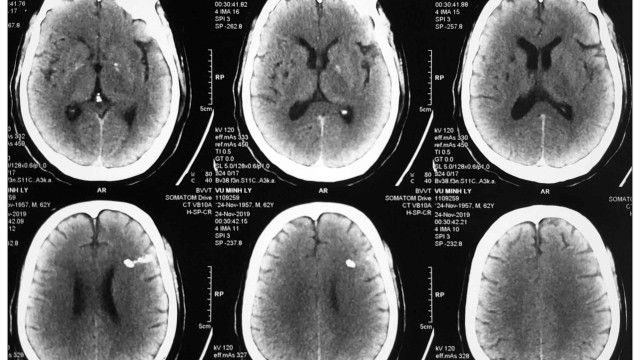

Chụp cắt lớp vi tính tưới máu não được chỉ định cho những trường hợp có nghi ngờ tổn thương não hoặc bất thường về hệ mạch máu nuôi dưỡng cơ quan này. Khi tiến hành, chuyên gia y tế sẽ kết hợp đồng thời việc dùng thuốc cản quang và phát tia X để ghi lại hình ảnh tại khu vực cần kiểm tra.